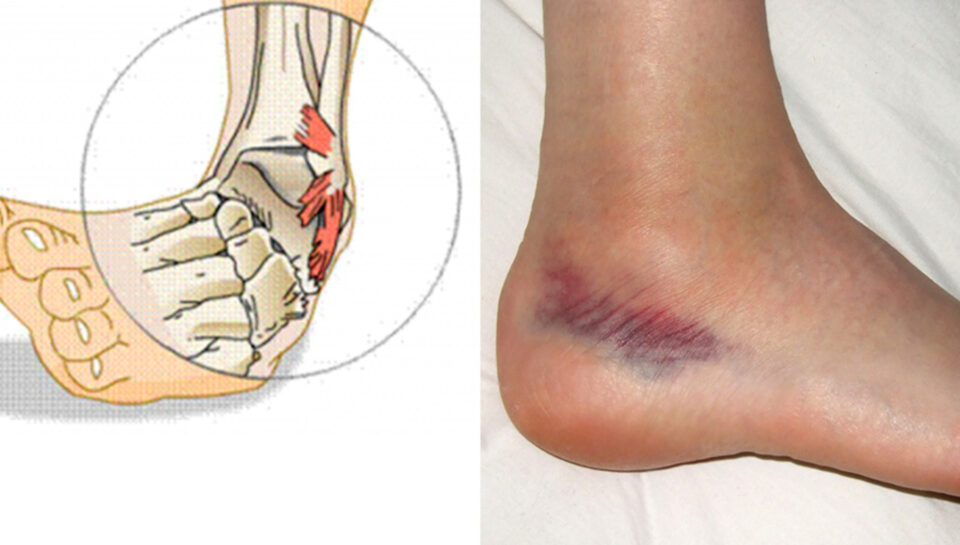

Distorsioni i kaviljes është një nga dëmtimet më të shpeshta, sidomos tek personat aktivë dhe sportistët. Ai ndodh kur kavilja përdridhet përtej kufijve normalë, duke dëmtuar ligamentet që stabilizojnë kyçin.

Simptomat

Simptomat ndryshojnë sipas shkallës së dëmtimit, por më të zakonshmet janë:

- dhimbje në zonën e kaviljes

- ënjtje dhe inflamacion

- vështirësi në ecje

- mavijosje

- ndjesi paqëndrueshmërie në këmbë